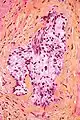

Invasion périneurale par un adénocarcinome prostatique. HE, x200